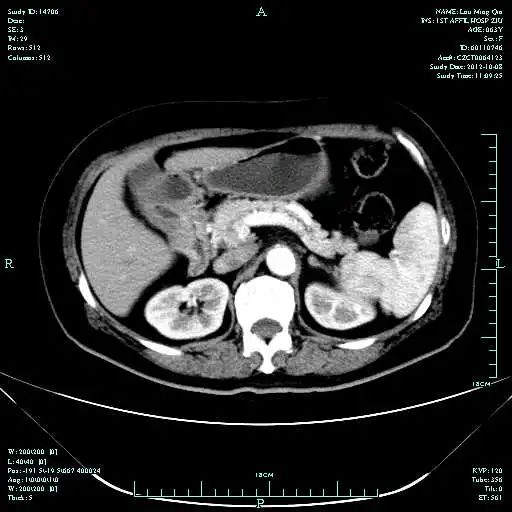

CT-T

影像学检查结果评估:cPD。